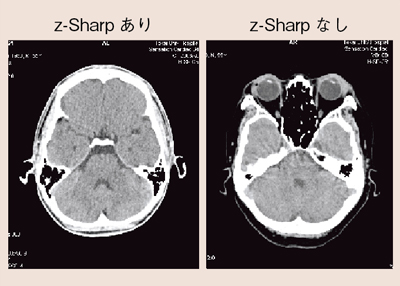

図9に,z-Sharpの有無による頭部の画像を示す。Windmillアーチファクトは,アキシャル画像で風車状に現れ,コロナルやサジタルでは,筋状になることが画像の異質感を生む。z-Sharpによりどの方向からでも同一の画質感で観察することができ,解像度の高いボリュームデータを得ることができる。これは,3D画像でも同様である(図10)。ボリュームデータを幅の広い照射野によって得ようとすると,X線ビーム幅が広がることにより,散乱線の影響や,線束中心と辺縁の空間分解能の違い,ヒール効果の影響による画像の劣化が表れてしまう。照射野を広げ過ぎずz-Sharpを用いることで,すべての位置において安定した高いボリュームデータを得ることができる。

図9 頭部におけるWindmillアーチファクトの影響